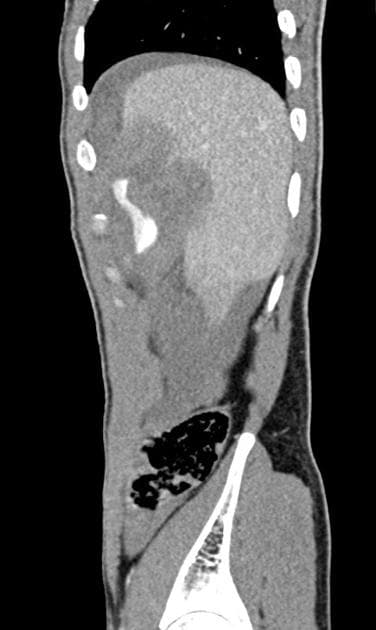

Có vùng giảm tỷ trọng (hypodense) dưới màng gan, tổ chức mô đệm không đồng nhất tại phân đoạn 3 gan. Vùng này nằm ngay dưới vị trí chèn dụng cụ nội soi tại vùng thượng vị trung tuyến, gợi ý vết rách do chèn dụng cụ. Có hiện tượng phồng màng gan tại chỗ, biểu hiện của một khối máu tụ nhỏ dưới màng gan. Vùng tổn thương có mật độ không đồng nhất, không đặc hiệu trên nghiên cứu một thì, và lan xuống phía các nhánh tĩnh mạch cửa trái. Khuyến cáo thực hiện chụp CT gan nhiều thì (multiphase CT) để loại trừ chảy máu hoạt động và các biến chứng mạch máu do vết rách.

Vết rách gan phân đoạn 3 nằm ngay dưới vị trí chèn dụng cụ nội soi thượng vị, lan dọc theo các nhánh của tĩnh mạch cửa trái (segment 3 hepatic laceration subjacent the epigastric port site and extends down the branches of the left portal vein). Không thấy xuất huyết hoạt động (active hemorrhage) trên nghiên cứu một thì, tuy nhiên do tổn thương gần các mạch máu gan và hình ảnh không đồng nhất, khuyến cáo đánh giá bằng chụp CT gan chuyên biệt nhiều thì để loại trừ biến chứng mạch máu (vascular complication).

Các tổn thương giảm tỷ trọng chưa xác định tại phân đoạn VI gan (indeterminate hypodense lesions segment VI of the liver) cũng có thể được đánh giá thêm trong lúc chụp CT gan nhiều thì.